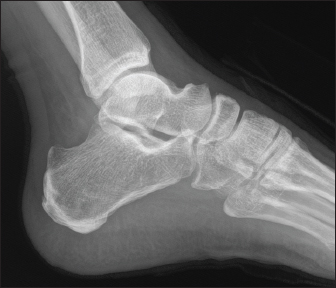

A 70-year-old male known to have diabetes mellitus presented with a 1 month history of fever and weight loss. History of multiple hospital visits and several courses of oral and intravenous antibiotics were present. Physical examination revealed hepatosplenomegaly. As he was fitting the criteria for Pyrexia of Unknown origin, work for the same was done. Routine investigations showed neutrophilic leucocytosis with raised inflammatory markers. Widal was negative. Ultrasound abdomen showed features of chronic liver disease. Contrast CT scan of abdomen showed splenic infarcts. He was started on antibiotics, but he had ongoing fever spikes. While in hospital he developed difficulty in walking due to left ankle pain. MRI foot (Fig. 1) was taken showed small intraosseous abscess in calcaneal bone. Blood cultures grew B. pseudomallei. The patient had a good recovery and was followed up in the outpatient clinic ray foot (Fig. 2) was repeated showed a resolution of osteomyelitis.

Fig. 1. MRI Rt foot—patient 1.